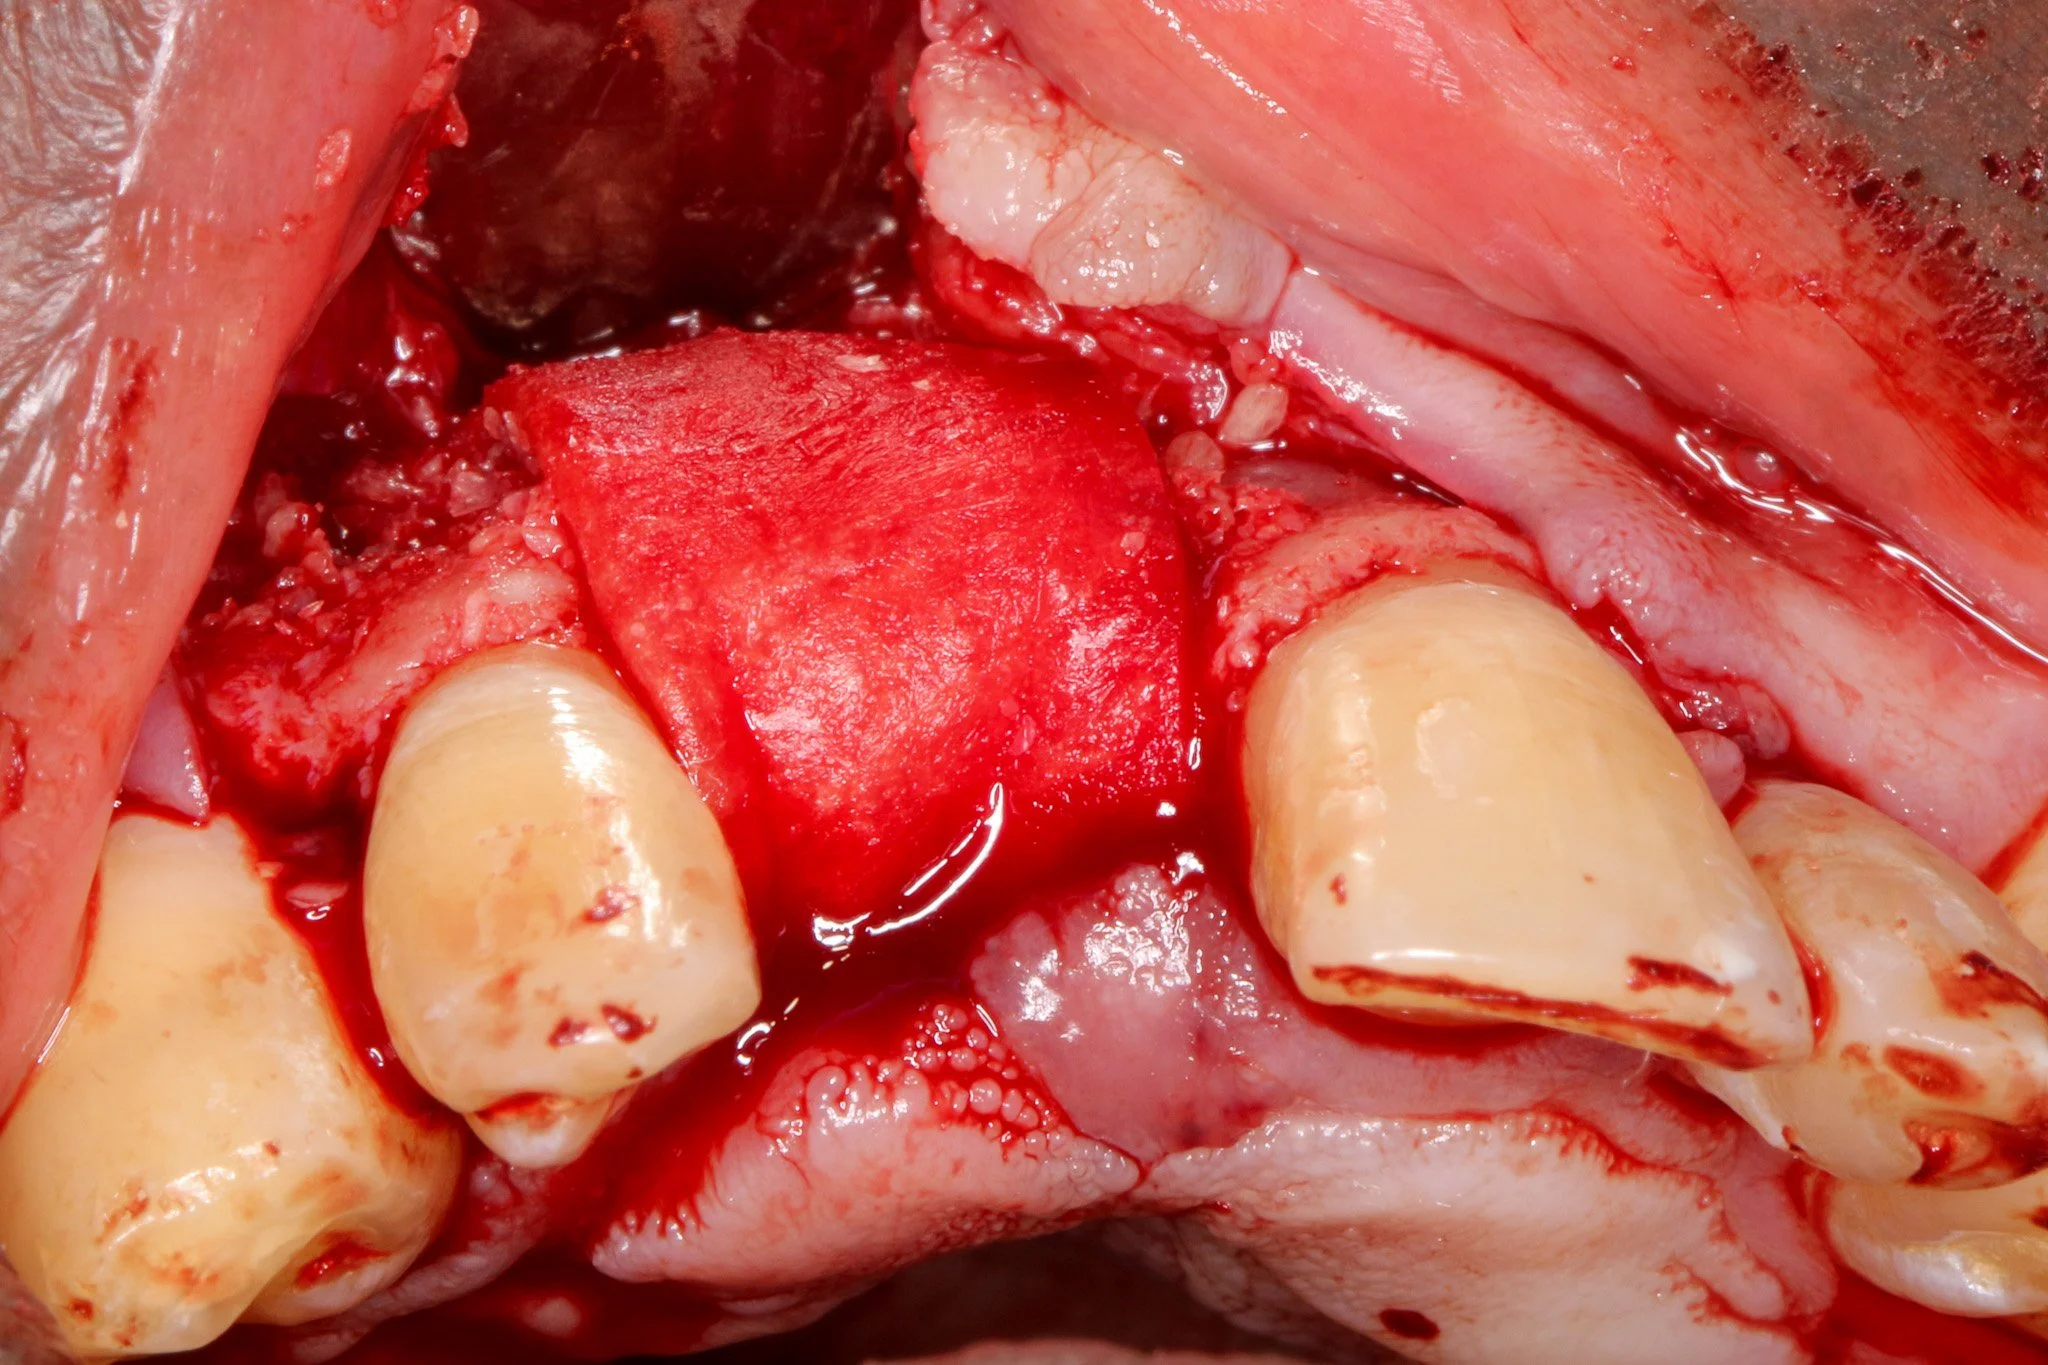

A double-layer resorbable membrane technique was employed with tacking srew fixation to ensure graft stability and space maintenance. The use of resorbable membranes has been extensively validated in the literature, with systematic reviews by Rocchietta et al. (2008) confirming comparable outcomes to non-resorbable membranes while eliminating the need for 2nd stage surgery. Urban et al. (2009), the dual-membrane approach provides enhanced barrier function and structural support.